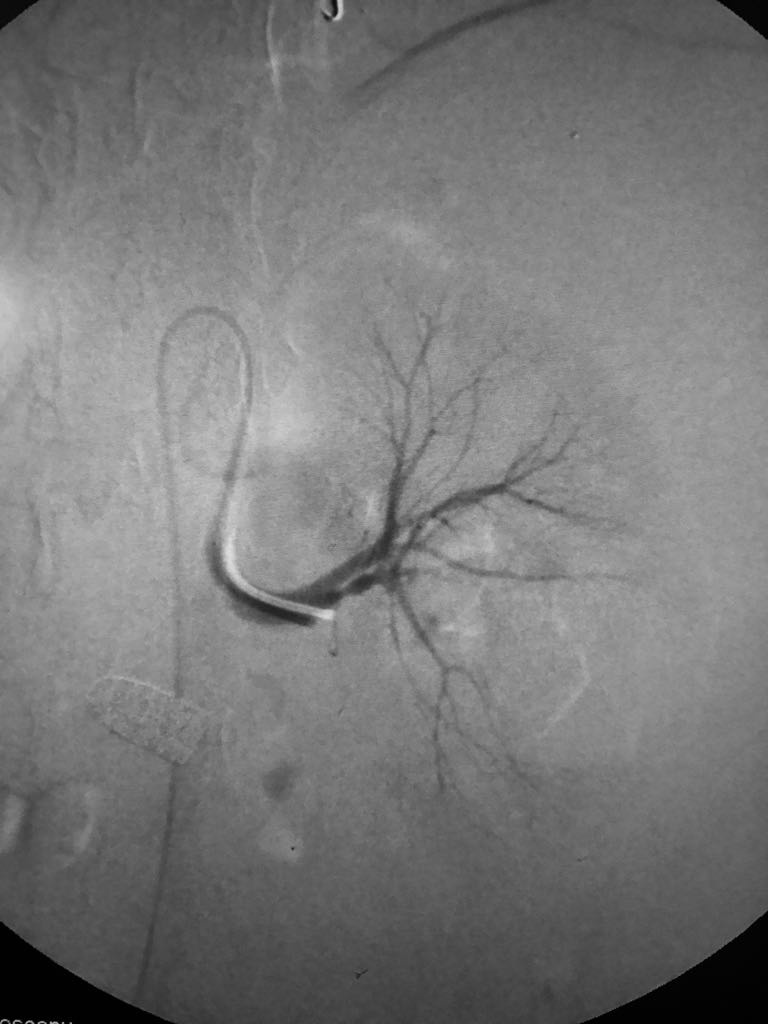

Somos una empresa enfocada en la atención en salud humana por medio del uso imágenes para ver diagnosticos y tratamientos de las diversas patologías con el uso de técnicas mínimamente invasivas en el territorio colombiano en el sector público y privado en búsqueda de una atención oportuna y de calidad a cada uno de nuestros pacientes.